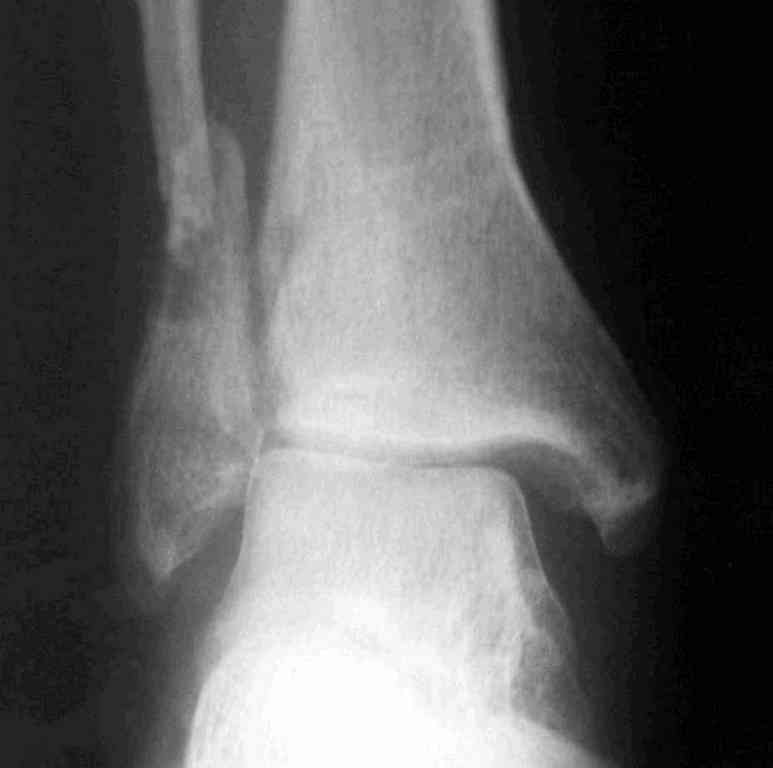

Уже 15 лет в отделении мы активно оперируем свежие переломы ГСС по принципам АО и вполне удовлетворены результатами лечения свежей травмы. В случаях же операций при позднем поступлении или реконструкции после неудачных вмешательств в ряде случаев сохраняется нестабильность ГСС, тенденция к вальгусной деформации. В свежих случаях никогда не приходилось производить шов дельтовидной связки, пластики тоже ни разу не выполнялись. Два примера на снимках.Первый - врач 38 лет, неудачно оперированный в своей больнице с двухлодыжечным переломом, разрывом МБС был повторно оперирован через 8 месяцев. Пытались восстановить длину наружной лодыжки остеотомией, освежили МБС, два месяца функционального лечения без нагрузки на стопу.Сейчас ходит с легкой хромотой, устает к обеду, вальгусное отклонение стопы корригировано супинатором. На Рграммах видны дистрофические изменения латерального эпифиза большеберцовой кости. Первый снимок через 6 месяцев после травмы, операции остеосинтеза болтом-стяжкой, удаленной по причине нестабильности и наличия свища над металлом. Второй снимок через 3 месяца после реконструктивной операции.

По снимкам в первом случае, укорочение малоберцовой приблизительно около 8-10 мм. Удовлетворительным восстановлением длины малоберцовой считается, когда на снимке суставная щель равны со всех сторон.